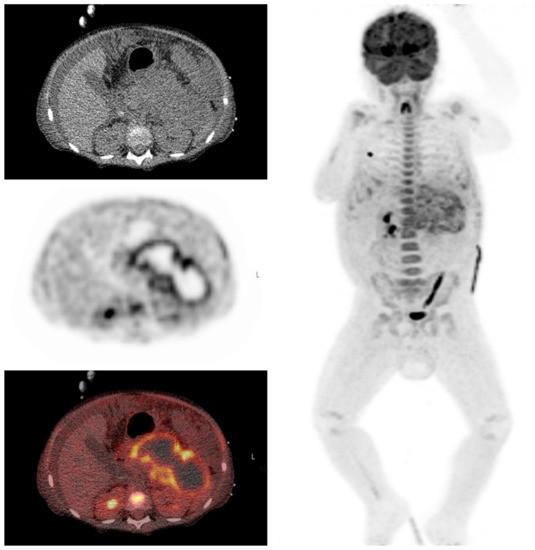

3.6. Clinical Examples